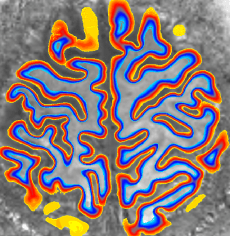

As a rule of thumb, every resampling step can lower the resolution by about the voxel size. This resampling dependent blurring has been reported in the literature from time to time and is gaining a lot of extra attention in the context of layer-dependent fMRI. Ville Renvall showed this effective resolution loss due to spatial resampling in the context of distortion correction in the supplementary material of his paper. Later, Jonathan Polimeni also showed it for motion correction.

Strategy 3: Applying spatial resampling on a finer grid than the voxel size

Since the resolution loss is a direct result from the signal redistribution of finite voxel sizes, it could be theoretically minimized by using a finer voxel grid. Finer than the effective resolution.